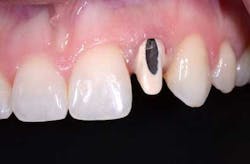

Fig. 1: There is a large access opening on the labial aspect of this UCLA abutment. The metal has been opaque and ceramic applied to allow the technician to use an all-ceramic restoration. Alternatively, a metal ceramic crown with a ceramic margin could be used.

Fig. 2: If the access opening is left open, the alloy and the shadow will lower the value of the crown, making it appear too gray.